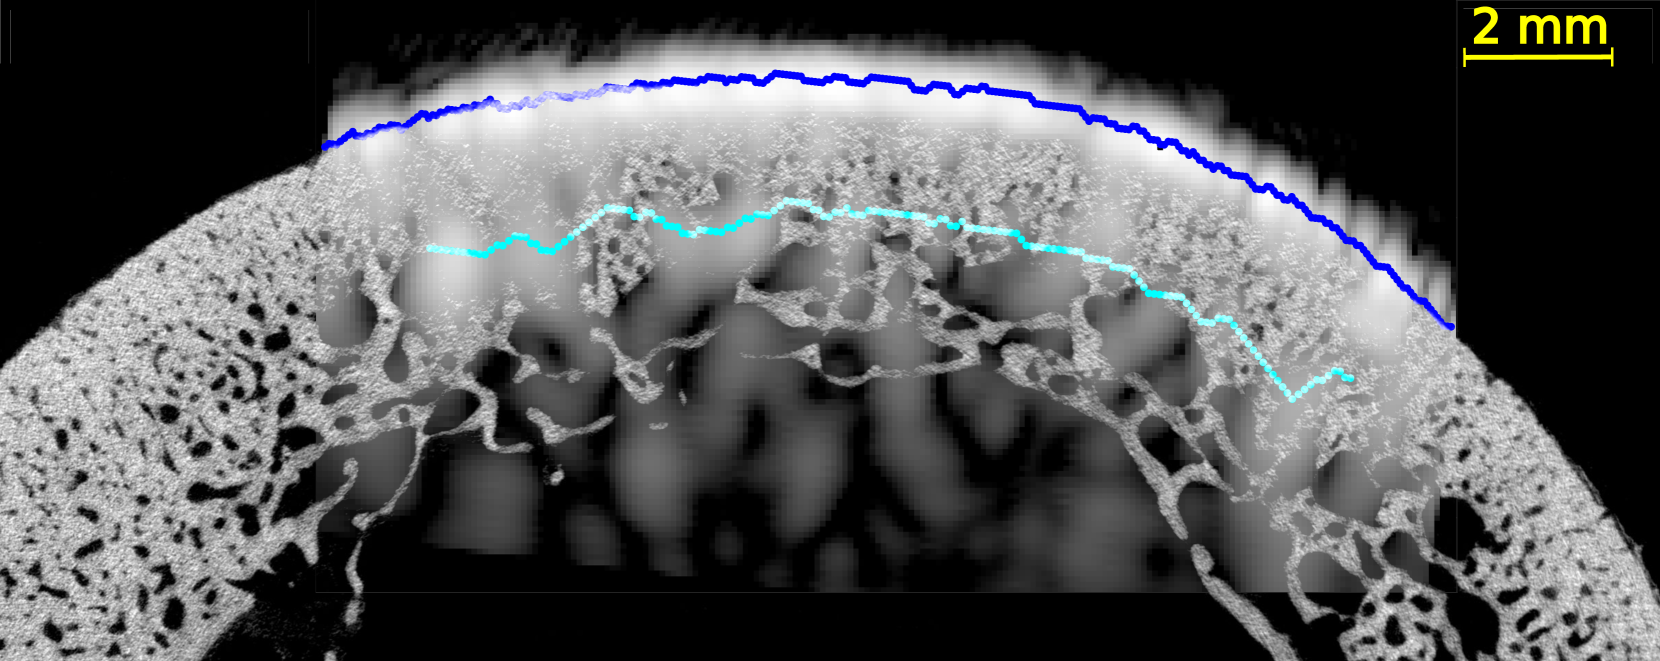

In all US images (Figure 4 and Figures S2-5 of supplementary materials), the periosteal surface appeared as a very bright line. The brightness of the endosteal surface was found to decrease with increasing porosity and with the presence of large pores. The endosteal surface was relatively bright in Samples 1 and 2 which had a small number of large pores and a small porosity; while the contrast of the endosteal surface was relatively weak in Samples 3 and 5 which had a higher porosity and some large pores near the endosteal surface (see the HR-µCT images (panels (a), (d), (g) and (j) of Figure 4). Segmentation with Dijkstra’s algorithm successfully delineated periosteal and endosteal surfaces for all measurement zones in all samples (see Figure 4). US images were aligned on HR-µCT images based on the periosteal surface segmentation. Periosteal surfaces from the US images accurately matched the periosteal surfaces segmented from the HR-µCT images: for all VOIs and all measurement repetitions, the root mean square error (RMSE) between the two segmentations was smaller than 0.3 mm, which value corresponds to half a US wavelength in water at 2.5 MHz (i.e., approximately the resolution limit).

We observed a good match between the segmented endosteal surface in the US image and the boundary of the cortex as seen in the HR-µCT image. The segmented endosteal surface closely followed the shape of the bone in the samples 1 and 2 which were the less porous and less heterogeneous. It is noteworthy that, despite the large thickness and complex geometry of sample 2, the endosteal surface was very bright in the US image. In the more porous and heterogeneous samples 3 and 5, the segmented endosteal surface followed the gross shape of the bone but was inside the cortex as seen in the HR-µCT image, above some large pores found close to the endosteal cortex boundary.

We evaluated the quality of US anatomical reconstructions and wave speed measurements across sixteen VOIs from bones of four individuals. Indeed, the bone of a fifth individual (sample 4) was too porous and heterogeneous to be effectively imaged through US. Our results indicate that the cortex boundaries and cortical thickness can be accurately determined for homogeneous and moderately porous VOIs, even for a thick cortex, as observed in samples 1 and 2 (mean thickness 2.9 and 5.9 mm and porosity between 5.0 and 12.3%, respectively). In these cases, the overlaying of US and HR-CT images showed that the segmentation of the surfaces in US images with the Dijkstra’s method closely aligns with the actual boundary, achieving thickness measurements with mean relative errors of 9 % and 4 %, respectively. In regions with higher porosity and larger pore diameters (samples 3 and 5 with porosity between 10.9 and 16.6% and Lg.Po.Dm between 224 and 307 m, respectively), the brightness of the endosteal surface is significantly reduced (from 7 dB to -5 dB). Nevertheless, Dijkstra’s algorithm was able to delineate endosteal boundaries that generally lied within the cortex, above the region with very large pores nearest to the endosteal surface. Consequently, in these cases, US-based cortical thickness measurements underestimated the reference (mean relative errors of 32 % and 47 %). However, for these highly remodeled bones with large resorption cavities leading to a trabecularization of the endosteal region, the delineation of the endosteal boundary as the end of the cortex and the beginning of the medullary canal is ambiguous, making it challenging to obtain a meaningful estimate of cortical thickness in the HR-CT images [5]. Another limiting factor in comparing cortical thicknesses determined from HR-CT and from US images lies in the slight differences in the regions of interest used for each VOI. The region of interest used for HR-CT images (Figure 2) were slightly larger than that used for US images. In the latter, as shown in Figure 4, the surfaces could only be reconstructed for a limited portion of the cortex due to the finite US probe aperture.

It is noteworthy that the inner cortex surface reconstructed with US was consistently within the bone, indicating that it effectively detects the most compact region corresponding to the tissue above the large pores in the endosteal region.

In highly porous samples exhibiting large pores, the reconstructed endosteal surface may show a reduced brightness and a lack of continuity. Indeed, previous simulations demonstrated that increased pore size has a strong detrimental effect on endosteal interface brightness [29], primarily due to the enhanced scattering by large pores. This ex vivo study corroborates these simulations results by providing an experimental proof that pore size is a major factor influencing intracortical US image quality.